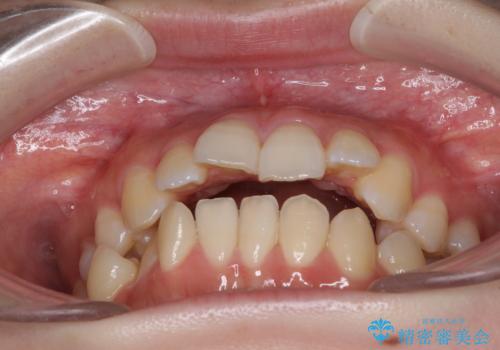

目立たない裏側矯正で突出感を改善 ハーフリンガル矯正

- 口元の突出感を気にして来院された患者様です。

上下左右の第一小臼歯4本を抜歯して口元を下げる治療計画としました。

裏側矯正特有の抜歯スペースに前後の歯が倒れ込む状態が長く続き、改善に長期間を要しました。